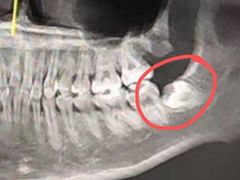

• 珠海市中西医结合医院

• -珠海市中西医结合医院